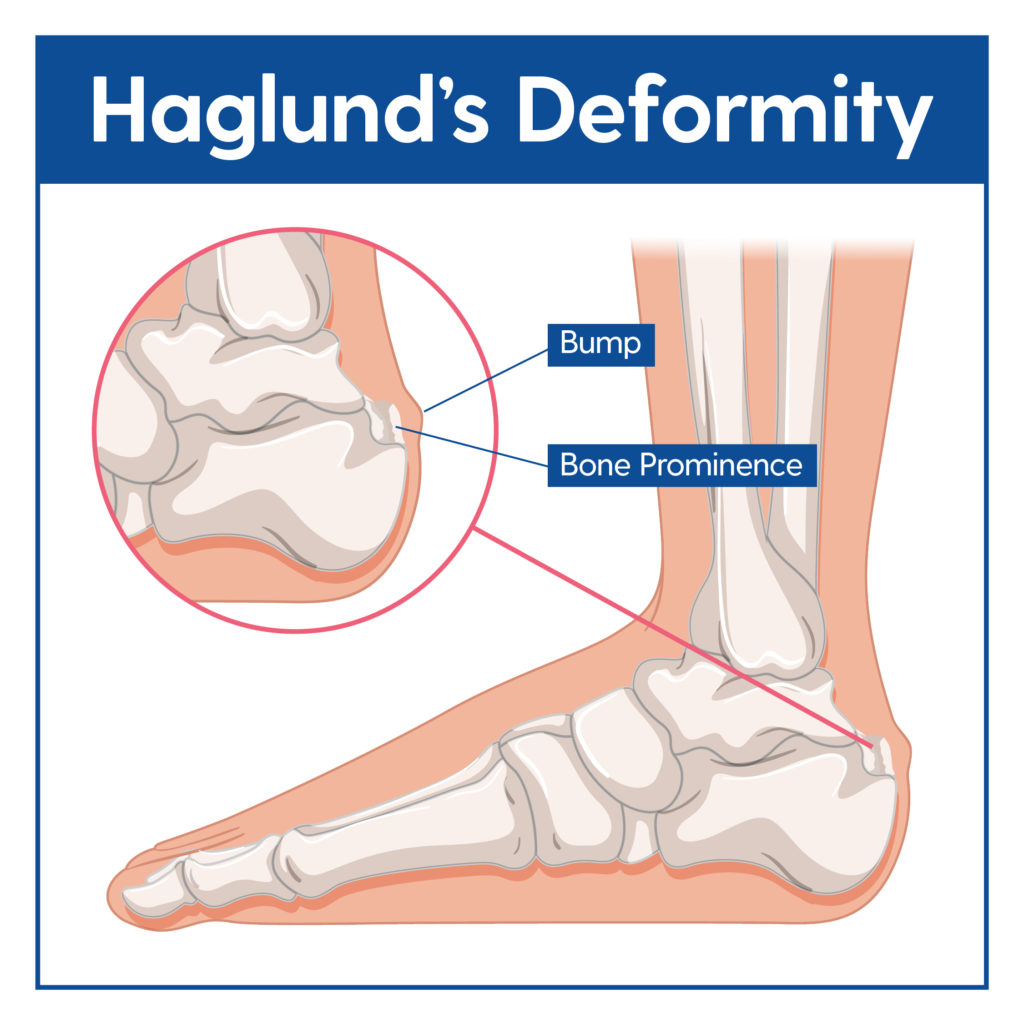

Haglund s Deformity Causes Treatment My FootDr